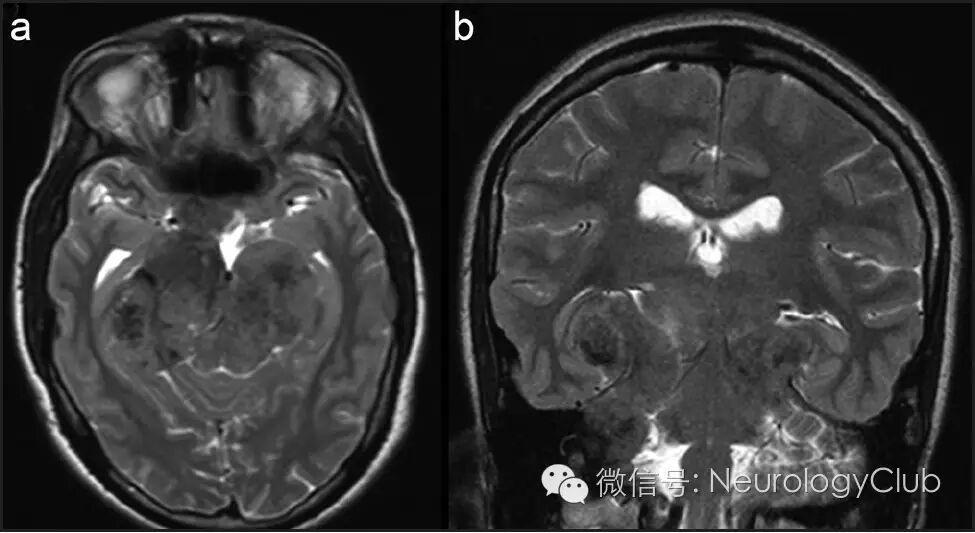

(图5:治疗后的T2WI。可见病灶明显低信号)

上颌窦病灶内镜活检提示非干酪样肉芽肿伴慢性炎性细胞浸润和浆细胞(图3)。患者血管紧张素转换酶升高(61.44U/l),高钙血症,结合组织病理学表现,诊断为神经结节病。免疫治疗6月,复查头颅MRI提示肉芽肿显著缩小(图4)伴T2明显低信号(图5)。临床上,患者步态和听力改善,目前生活可自理。